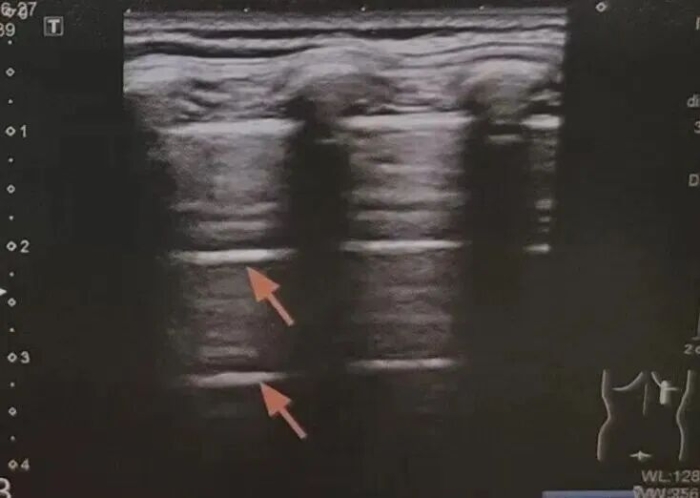

B线: 从胸膜发出、像激光束一样垂直向下延伸的线。B线增多,提示肺里有间质水肿或炎症,也就是我们常说的“肺水多了” 。

新生儿呼吸窘迫综合征超声表现为双肺弥漫分布的密集B线,双肺近胸膜下小片状肺实变。